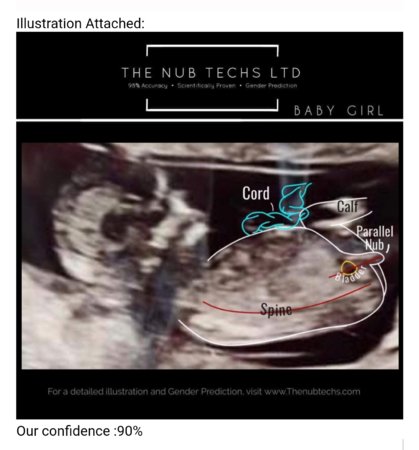

Wow, kaikkea sitä onkin jo keksittyMähän hairahduin ja ostin netistä nub techs nimiseltä firmalta ennusteen sukupuolesta :DView attachment 84016

Tämän mukaan tyttö olisi tulossa![]()

Minä täällä salaa takapiruilen teidän suurperheellisten eloa. Itselläni on vain yksi biologinen lapsi, mutta miehellä kaksi ja vielä tähän hullunmyllyyn yhteistä kuumeillaan.Kustansi 9,99 puntaa, eli noin 12e. :) Joo, tää oli tuolta salaisten ryhmästä bongattu, joku muukin teki ja sai 85% varmuudella tyttö vastauksen. Nyt sit mietin et oonko kuitenkin kysymättä rakenneultrassa vai kysynkö varmistuksen :D